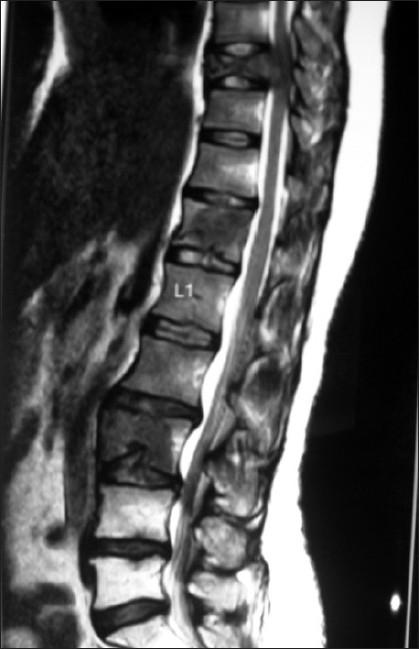

一名绝经前女性患有多器官转移的子宫内膜样腺癌。

Endometrioid endometrial adenocarcinoma in a premenopausal woman with multiple organ metastases.

Endometrial adenocarcinoma is the third common malignancy of the female genital tract occurring most often in the postmenopausal age group. High tumor grade, advanced surgical stage, and lymphovascular space invasion are implicated as poor prognostic factors for dissemination of disease. We present an unusual case of endometrial adenocarcinoma in a premenopausal woman with simultaneous metastases in brain, liver, skin and skeletal system, within one month of completion of treatment. The role of adjuvant/concurrent chemotherapy in addition to radiotherapy in high risk cases is discussed along with the review of literature.

子宫内膜腺癌是女性生殖道第三常见的恶性肿瘤,最常发生于绝经后年龄组。高肿瘤分级、手术分期晚以及淋巴管间隙浸润被认为是疾病播散的不良预后因素。我们报告了一例绝经前女性子宫内膜腺癌的罕见病例,在完成治疗后的一个月内,脑、肝、皮肤和骨骼系统同时出现转移。本文结合文献复习,讨论了高危病例中辅助/同步化疗联合放疗的作用。